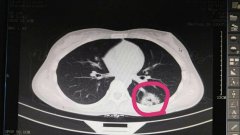

日前,我院急診科接到120通知,接回一車禍病人,入院時(shí)表述胸腹部疼痛,并呈現(xiàn)出血壓下降……